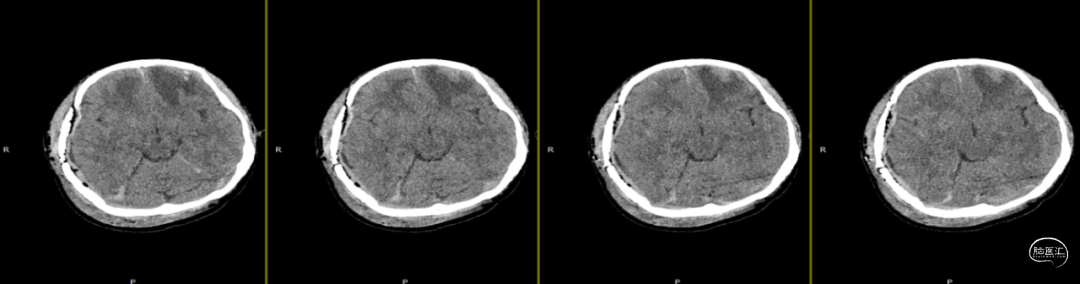

查体:嗜睡-昏睡状态,精神差,刺激睁眼,简单应答,肢体活动简单从嘱。GCS13分。双侧瞳孔等大等圆,直径2.5mm,对光反射灵敏,伸舌欠合作。转头、耸肩欠合作,四肢肌力4级,肌张力正常,颈抵抗(+),双Babinski sign未引出。枕部可见约5*4cm皮下血肿,压痛,拒按。周身多发片状皮肤擦伤。颅脑CT:双侧额叶脑挫裂伤;右侧顶颞枕部硬膜外、硬膜下血肿;蛛网膜下腔出血;右侧颞骨骨折累及右侧人字缝、顶乳缝,右侧顶乳缝旁小骨片;头皮软组织损伤、局部皮下血肿;双肺挫伤可能。

因患者在病情观察期间意识状态变差,昏睡-浅昏迷状态,予以急症手术治疗,清除硬膜外血肿,鉴于术中脑组织压力不高,予以骨瓣回置,术后严格控制血糖水平,常规使用抗生素(头孢唑林钠)预防感染。

术后第1天颅脑CT复查(如上图)